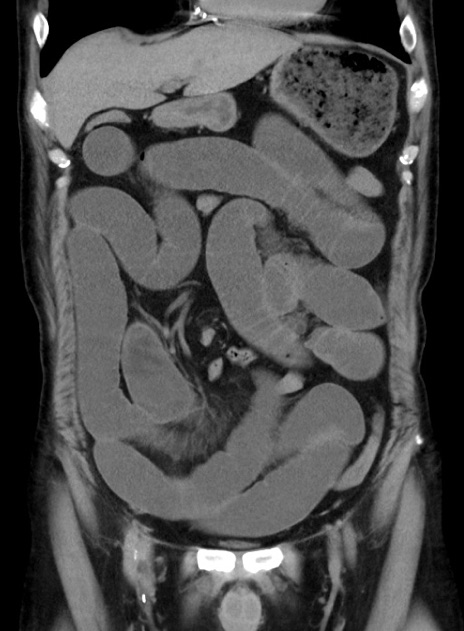

症例38(冠状断像)

【症例】70歳代 男性

【主訴】腹痛・嘔吐

【現病歴】昨晩より、嘔吐・腹痛あり。今朝になっても嘔吐あり。来院。

【既往歴】心臓バイパス手術、開腹胆摘、腸閉塞

【身体所見】BP 107/71mmHg、HR 116/min、腹部:平坦、軟、下腹部に軽度圧痛あり。反跳痛なし。

【データ】WBC 15100、CRP 0.32